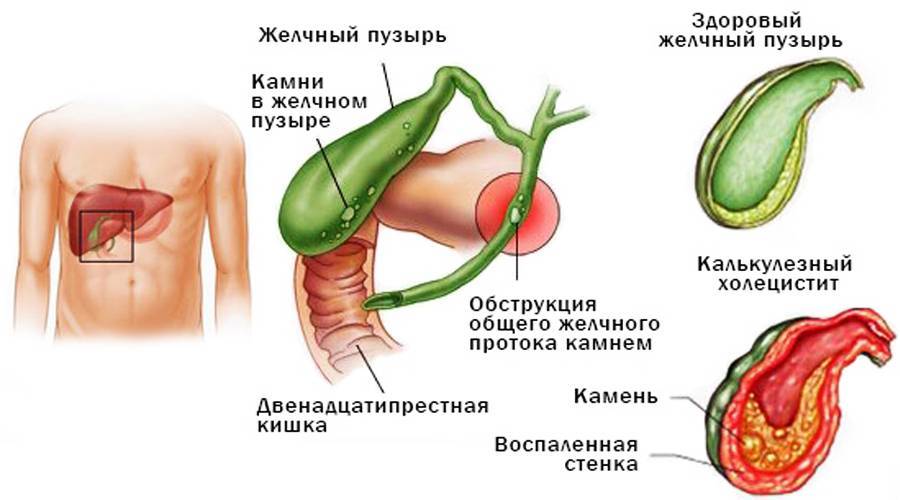

Анатомия и особенности Гартманова кармана желчного пузыря